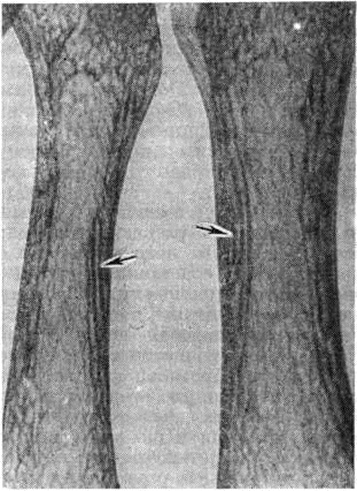

Увеличение количества и толщины костных трабекул при Остеопатия нефрогенная обусловливает рентгенологическую картину остеосклероза. Прежде всего это наблюдается в телах позвонков, где плотные полосы чередуются с более прозрачными. Остеосклероз можно отметить также в рёбрах, черепе и трубчатых костях. Одним из рентгенологических проявлений остеомаляции являются зоны перестройки костной ткани (зоны Лоозера). На снимке они видны как перпендикулярные к корковому слою светлые полосы, напоминающие перелом. Зоны перестройки можно обнаружить в ключице, костях таза (рисунок 3) и длинных трубчатых костях. Остеомаляция может привести к деформации вертлужной впадины. У некоторых больных, долгое время леченных гемодиализом, уменьшается масса костной ткани и появляются переломы. Вторичный гиперпаратиреоз может дать картину фиброзного остеита с очаговым уплотнением кости. Наряду с резорбцией кости происходит образование новой кости. Это наблюдается главным образом у больных, длительно леченных гемодиализом. Периостальное образование новой кости имеет вид тонкой пластинки, отделённой от периоста. У больных после пересадки почки и длительно леченных гемодиализом может наблюдаться остеонекроз (рисунок 4). Степень минерализации костей может быть определена прижизненно методом рентгеноденситометрии (смотри полный свод знаний).